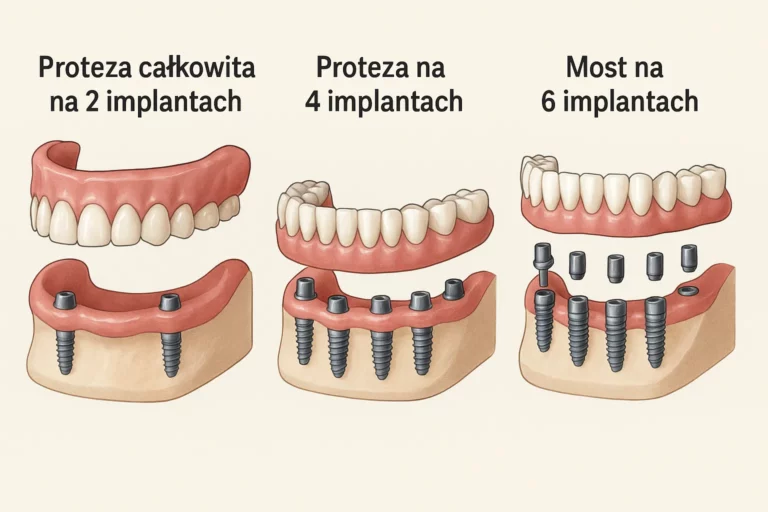

Ile kosztuje implant zęba, a ile cała szczęka? Czy zabieg boli i jak długo trwa leczenie? Ta kategoria to centrum wiedzy o implantach, odpowiadające na najważniejsze pytania pacjentów. Znajdziesz tu szczegółowe informacje o implantacji natychmiastowej, nawigacji komputerowej, metodach All-on-4, a także o zaawansowanych zabiegach odbudowy kości (augmentacji) i podnoszenia dna zatoki.

Belka na implantach to zaawansowany element protetyczny, który rewolucjonizuje sposób stabilizacji protez dentystycznych. Dzięki tej technologii…

Proteza na implantach w jeden dzień to nowoczesne rozwiązanie, które pozwala na szybkie odzyskanie pełnego uśmiechu….